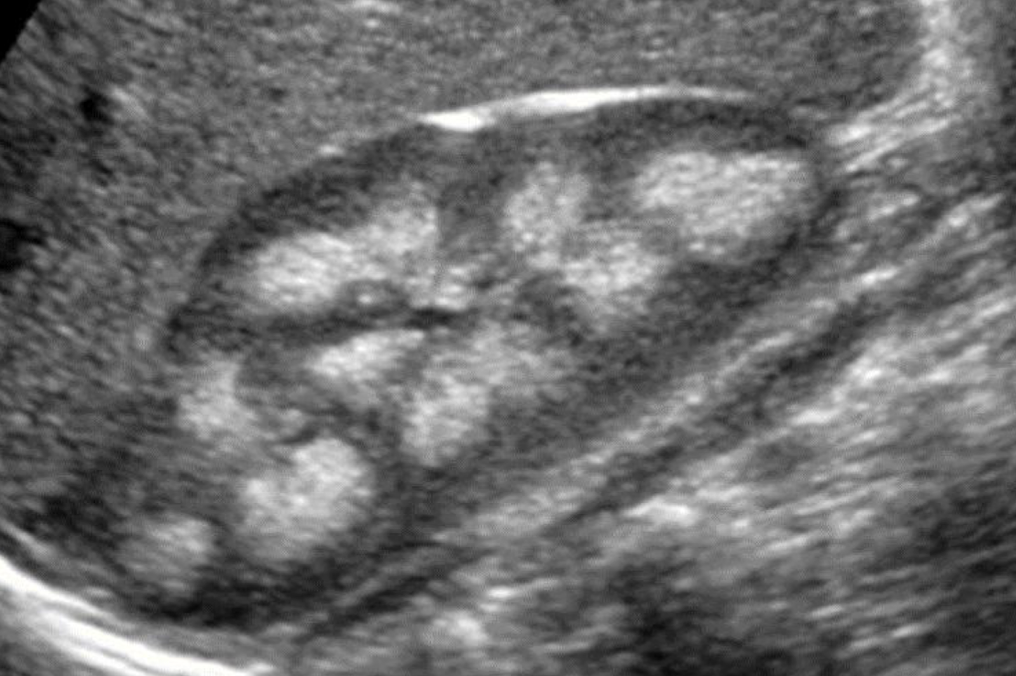

autosomal dominant polycystic kidney disease (ADPKD)

ADPKD1 is MC and found on the short arm of 16th chromosome (affects kidney more severely)

severity varies depending upon the genotype

manifest around 40-50 y/o

s/s: pain; HTN; hematuria; headache; UTI; palpable mass; renal insufficiency

family history and tissue sampling is required for dx confirmation

high incidence of urolithiasis and RCC in dialysis patients

SONO (neonates vs. adults): autosomal recessive polycystic kidney disease (ADPKD)

neonates:

enlarged kidneys

adults:

enlarged kidneys with asymmetrical cysts in cortex and medulla

loss of reniform shape (kidney shape)

?? describe

autosomal dominant polycystic kidney

“multiple cystic structures noted throughout RK. ?polycystic kidney dz”